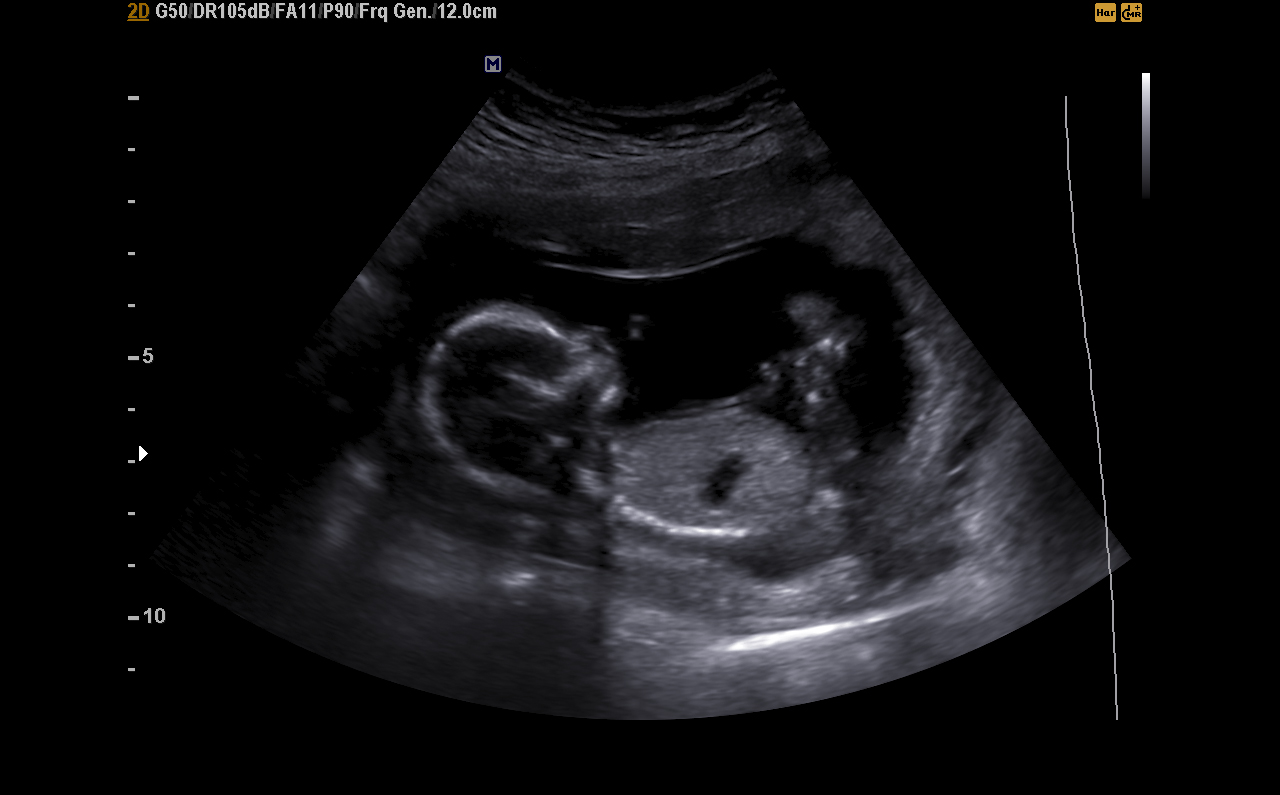

This is a friends 15 week ultrasound, the lady gave her a 95% but she still didn't seem confident.

I'm going to guess boy.....but I feel like a potty shot would be more accurate

I don't see any gender clues here. I hope the tech had more to go on.